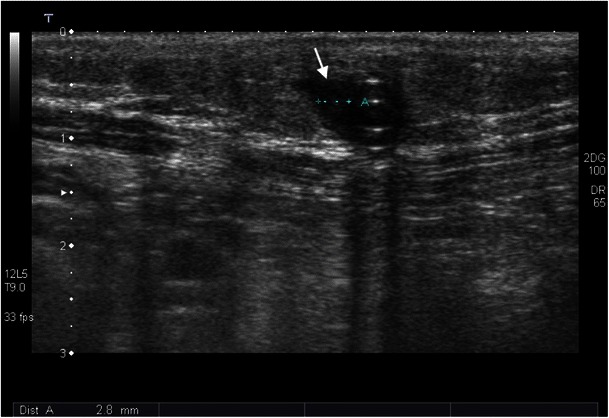

Fig. 13.

In a 51-year-old male patient with elevated inflammatory laboratory parameters, ultrasound examination shows a hypoechoic structure along the dialysis catheter in the subcutis, which corresponds to inflammatory changes (white arrow)